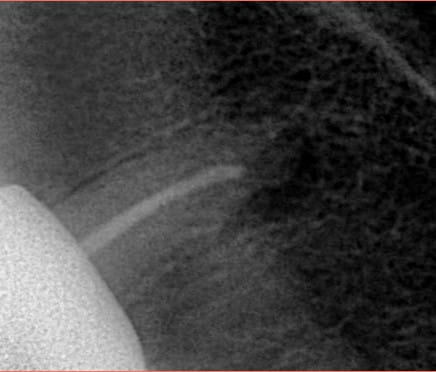

Tooth no23 with more than 14 years old filling.this type of treatment was good at its time and circumstances .Today, it is preferable to choose a treatment that reduces the risk of catastrophic failure and preserves the tooth structure for future interventions if anything goes wrong , as this will prolong the TOOTH’s longevity.